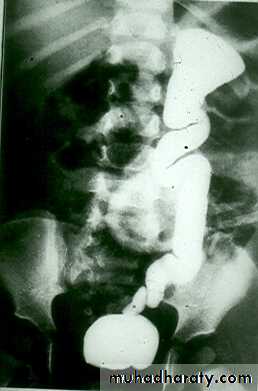

I.V.U. shows :

* Marked dilatation of pelvis and may be extra-renal .

*Calyceal dilatation is late and in advanced cases produce parenchymal atrophy .( foot shape pcs ) .

* The ureter is not seen and when it is seen looks normal .

* Delayed film with I.V. diuretic produce gross dilatation .

CONGINTAL HYDRONEPHROSIS

( PUJ obstruction )